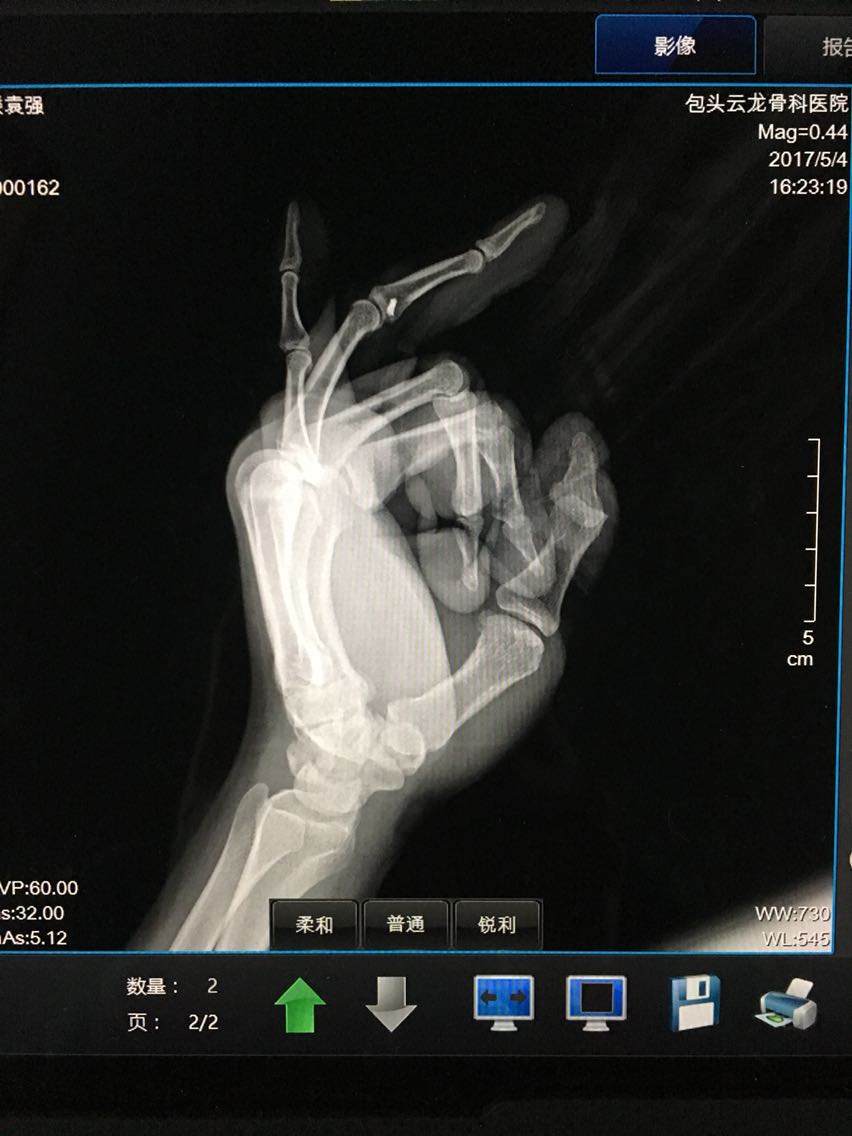

主诉:左手环指外伤后畸形伴功能障碍1小时余。 病史:患者M/30,1小时前与他人发生争执被他人扭伤左手环指,出现疼痛、畸形伴功能障碍。

查体:左手指体肿胀,近指间关节以远指体尺偏畸形,近指间关节体表触压痛阳性,近指间关节尺侧侧方应力试验阴性,桡侧侧方应力试验阳性,被动伸指成过伸样改变。

诊断:左手环指近指间关节脱位并关节囊、侧副韧带、掌板断裂 治疗:切开桡侧副韧带、关节囊缝合修复术及掌板止点金属骨锚钉重建修复术